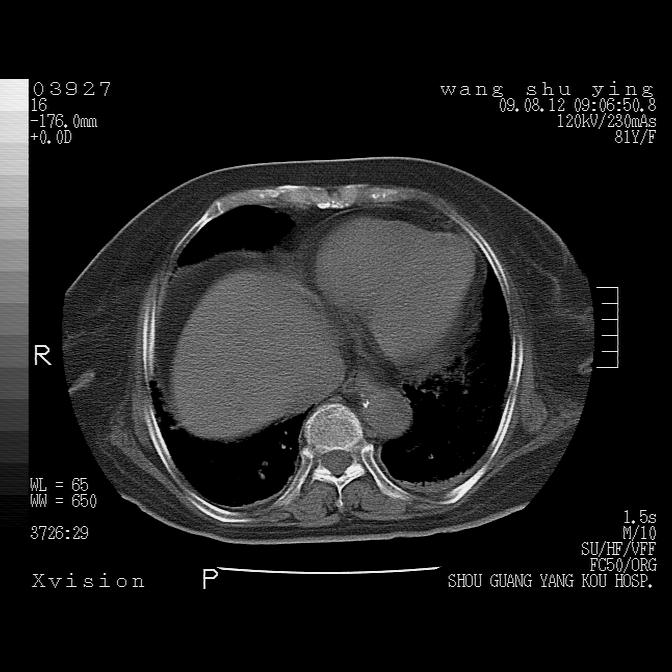

以下是引用帅河马在2009-8-12 12:59:00的发言:[br]两肺感染性病变伴双侧胸膜肥厚。[br]左侧甲状腺腺瘤不除外。[br]腹水+心包积液。[br][br][本贴已被 帅河马 于 2009-8-12 13:14:32 修改过]

以下是引用sdzyy在2009-8-12 18:17:00的发言:[br]两肺感染性病变伴双侧胸膜肥厚。[br]左侧甲状腺腺瘤不除外。[br]腹水+心包积液。[br]支持

以下是引用随光逐影在2009-8-12 19:42:00的发言:[br]1)两肺感染性病变伴双侧胸膜肥厚。2)不排除左侧甲状腺腺瘤。3)肝脏占位性病变;建议行进一步检查。